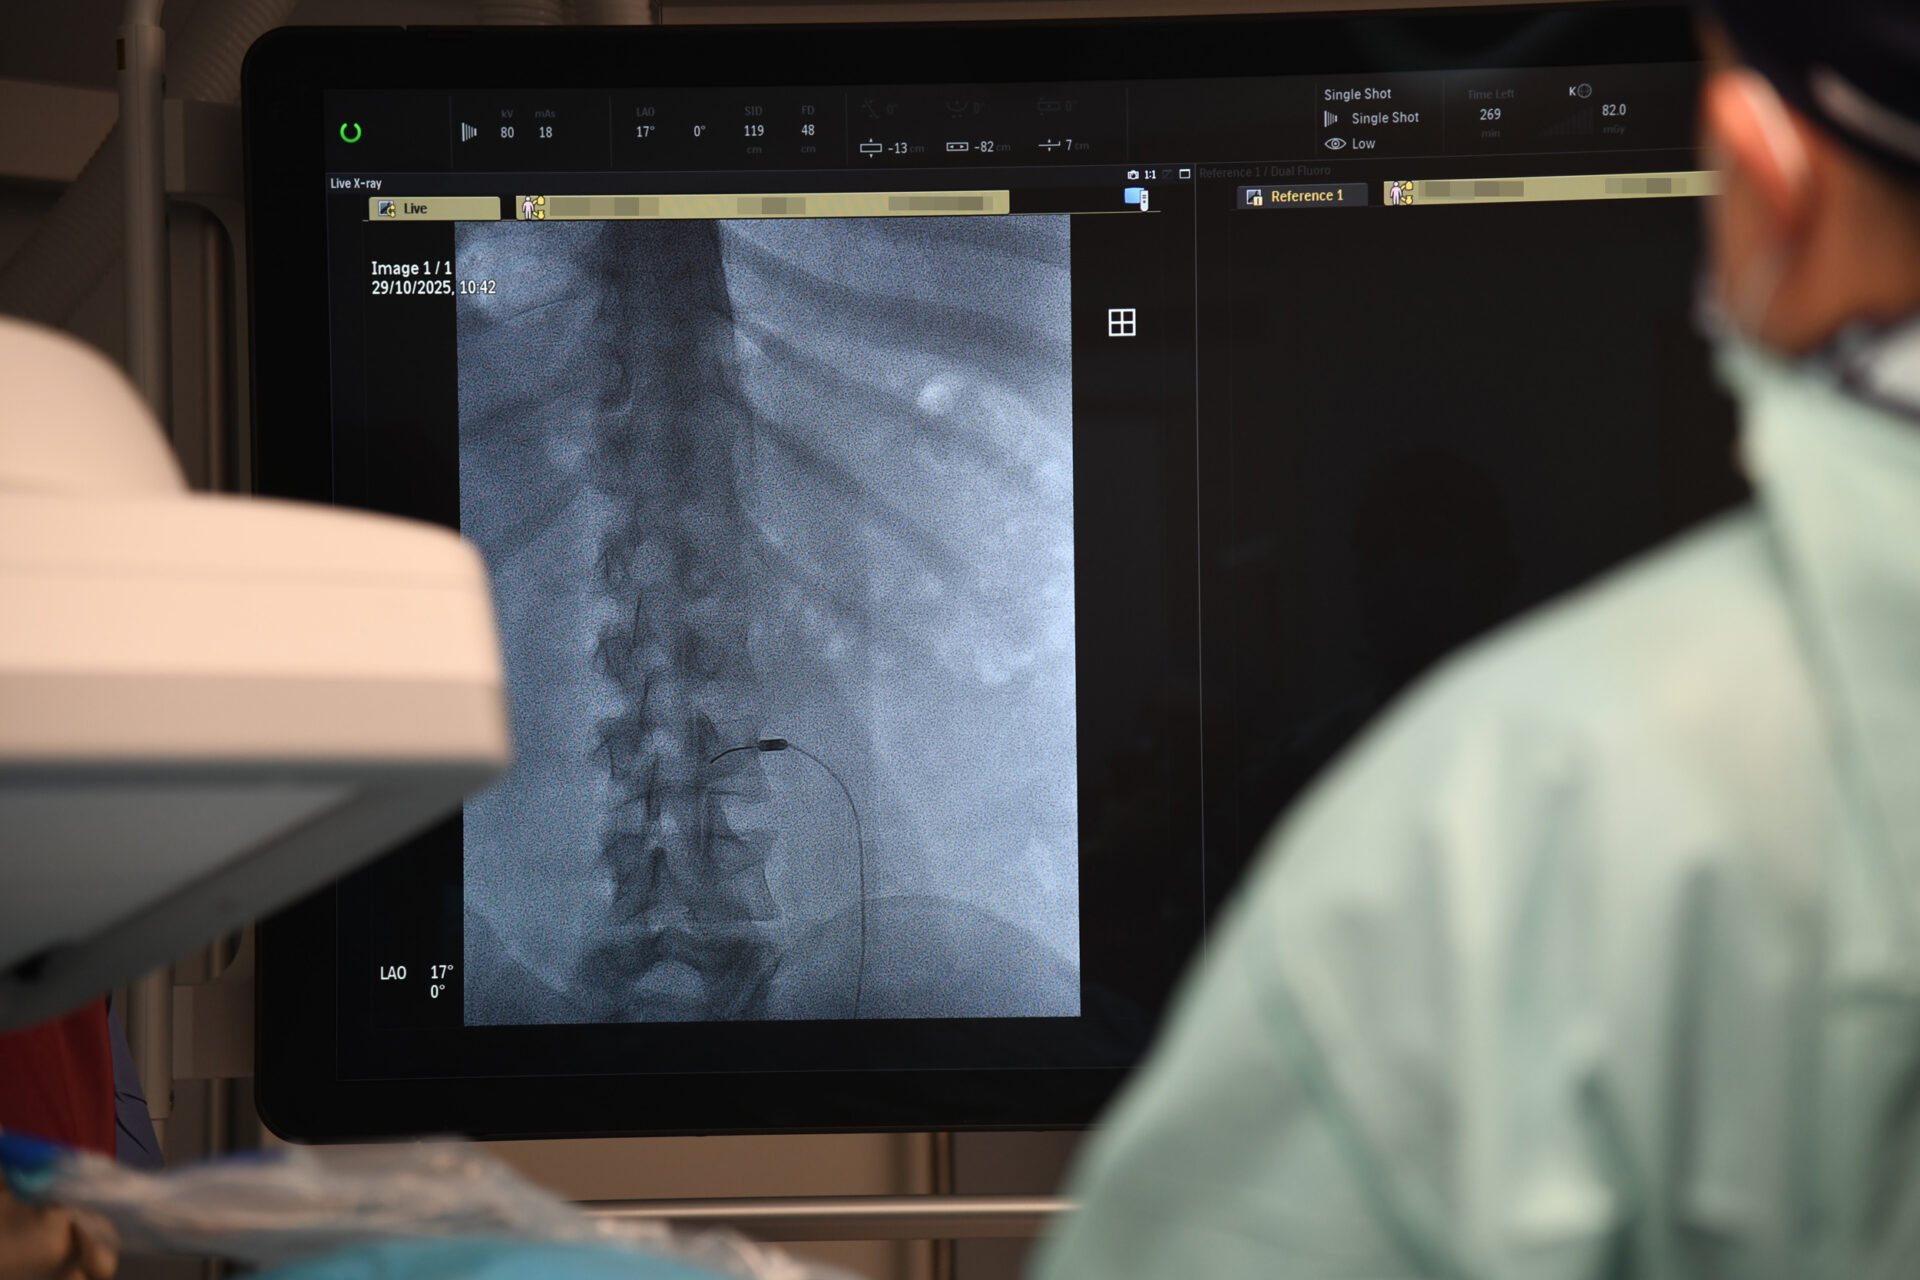

– Z przeciążenia stawów międzykręgowych. Co można wtedy zrobić? Zniszczyć unerwienie tych stawów. Robimy to wbijając igłę, pod kontrolą prześwietlenia rentgenowskiego, bo jest to metoda wymagająca precyzji. Do igły wprowadzamy emiter prądów wysokiej częstotliwości i nagrzewamy tkanki do temperatury – w tym konkretnym przypadku – 85 stopni Celsjusza. Nagrzewamy miejscowo tylko tę strukturę, która nas interesuje, bo pole rażenia tej elektrody jest niewielkie – tłumaczy lekarz.

Wysoki poziom wykonywania termolezji w słupskim szpitalu jest możliwy dzięki używanemu sprzętowi wysokiej klasy np. nowoczesnemu angiografowi zakupionemu przez szpital na początku 2025 r.